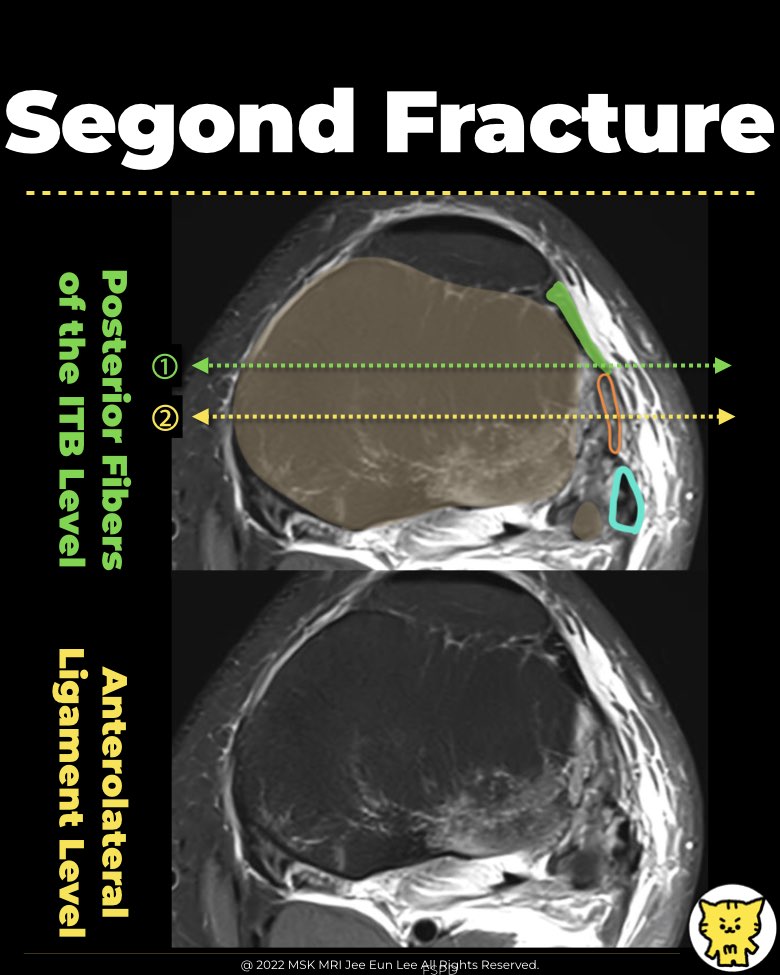

- A specific avulsion fracture on the lateral aspect of the proximal tibia, near the tibial plateau.

- Typically thin, ovoid, and vertically oriented, located anterolaterally or laterally along the lateral tibial plateau, posterior to Gerdy's tubercle.

✅ Segond Fracture Site

- The Segond fracture fragment is typically thin, ovoid, and vertically oriented, located anterolaterally or laterally along the lateral tibial plateau, posterior to Gerdy's tubercle.

- This fracture occurs at the location of the tibial insertion of the anterolateral ligament (ALL).